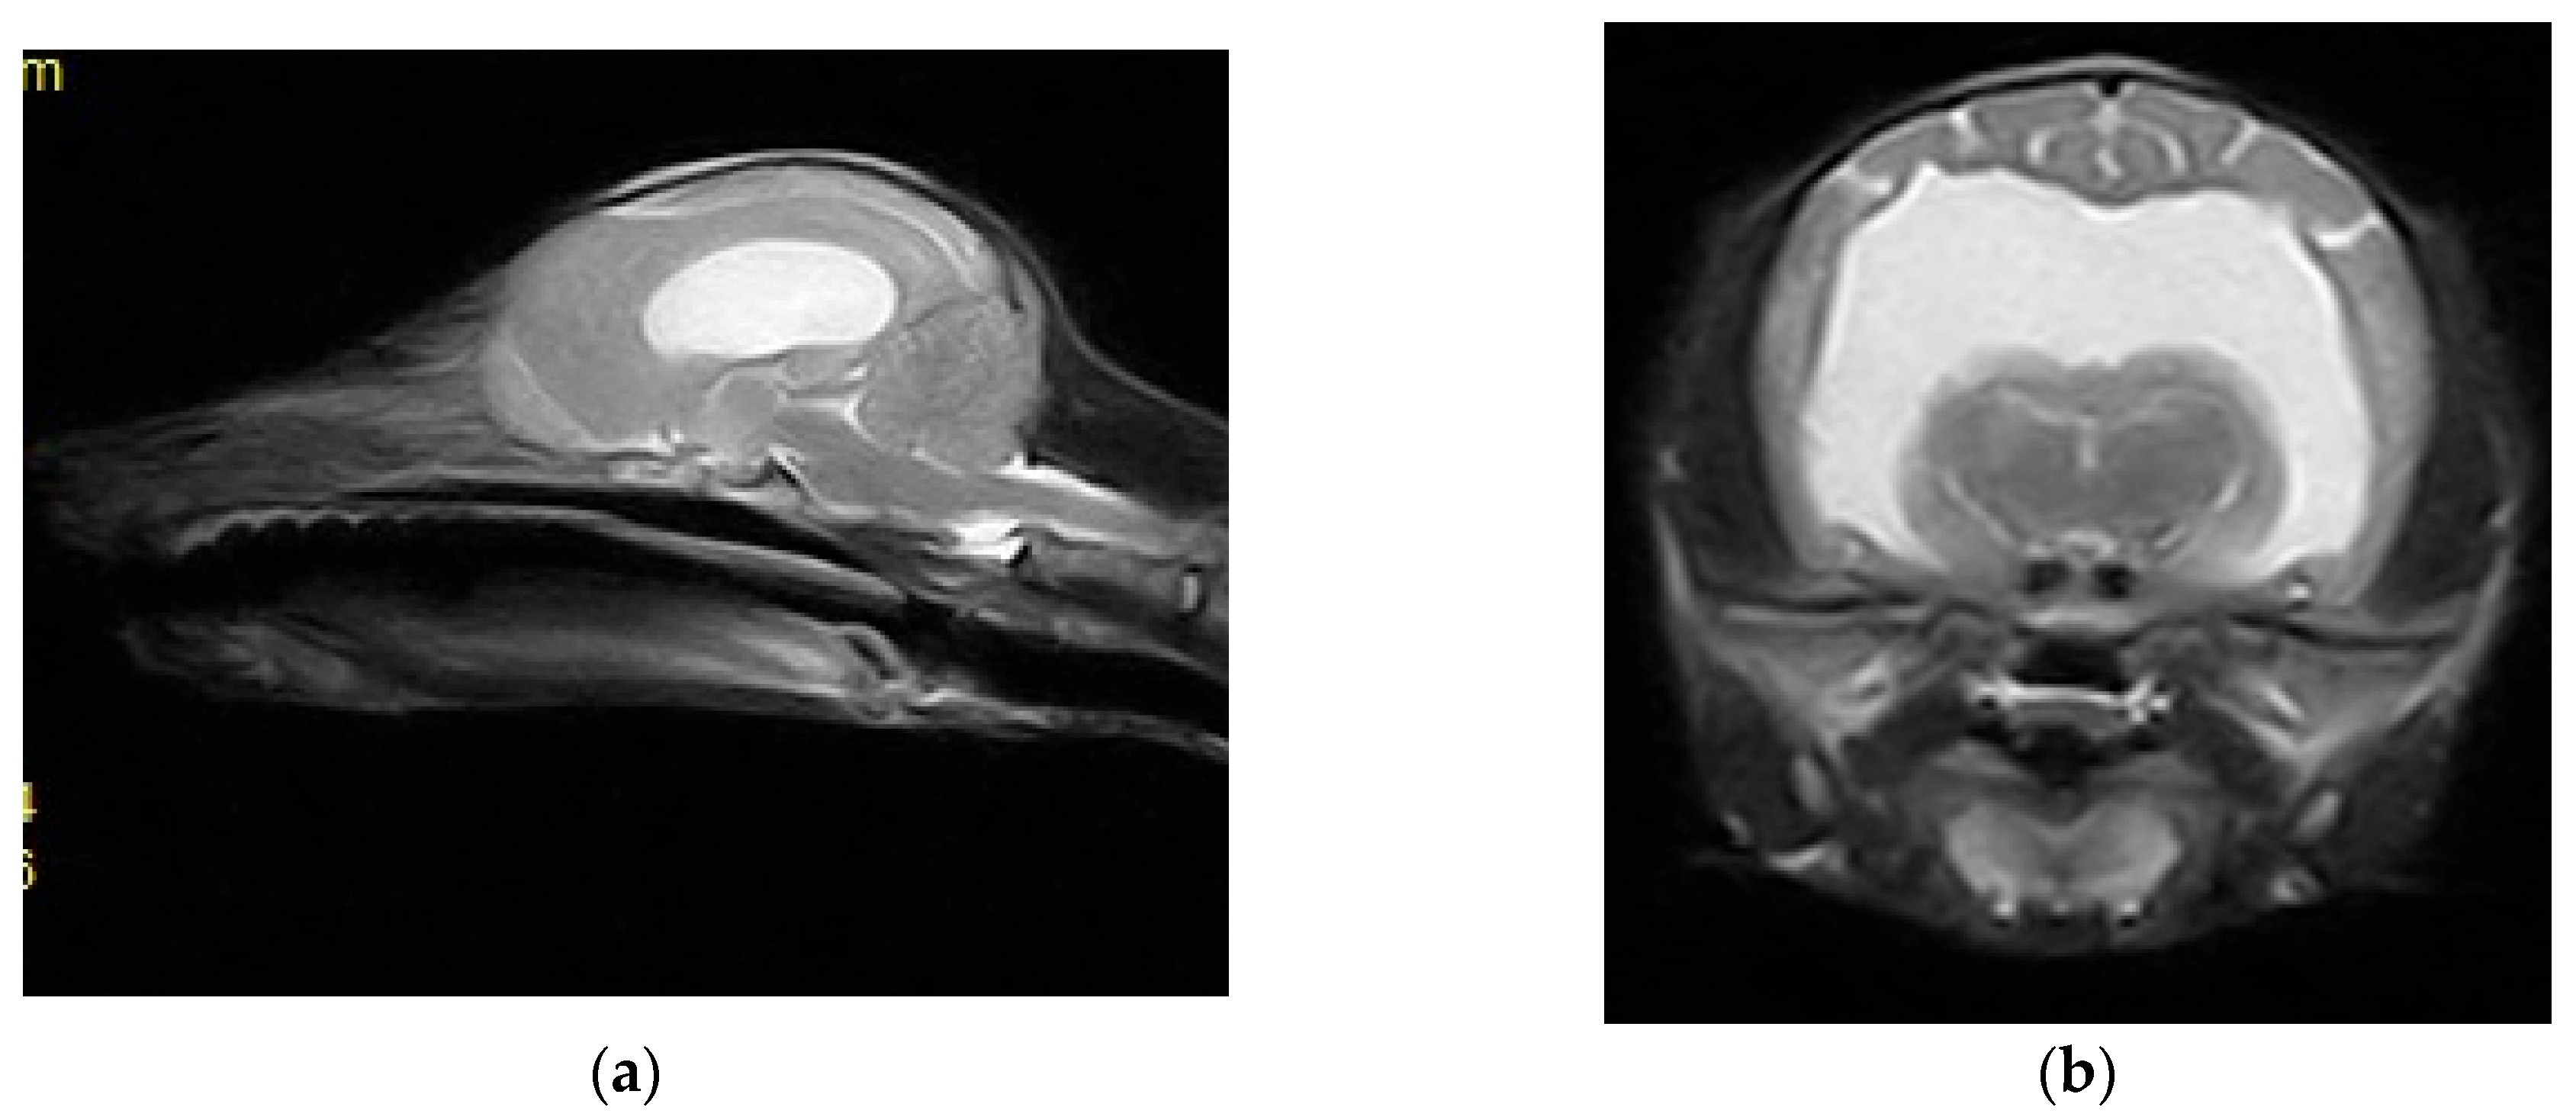

Imaging Diagnosis of Hydrocephalus in a Fox Cub-Case Study

2. Case Description